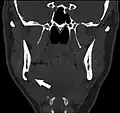

Coronal computed tomograph of the same person (Stafne defect arrowed).

Stafne's defect is usually discovered by chance during routine dental radiography.[11] Radiographically, it is a well-circumscribed, monolocular, round, radiolucent defect, 1–3 cm in size, usually between the inferior alveolar nerve (IAN) and the inferior border of the posterior mandible between the molars and the angle of the jaw. It is one of the few radiolucent lesions that can occur below the IAN. The border is well corticated and it will have no effect on the surrounding structures. Computed tomography (CT) will show a shallow defect through the medial cortex of the mandible with a corticated rim and no soft tissue abnormalities, with the exception of a portion of the submandibular gland. Neoplasms, such as metastatic squamous cell carcinoma to the submandibular lymph nodes or a salivary gland tumour, could create a similar appearance but rarely have such well defined borders and can usually be palpated in the floor of the mouth or submandibular triangle of the neck as a hard mass. CT and clinical exam is typically sufficient to distinguish between this and a Stafne defect. The Stafne defect also tends to not increase in size or change in radiographic appearance over time (hence the term "static bone cyst"), and this can be used to help confirm the diagnosis.[11] Tissue biopsy is not usually indicated, but if carried out, the histopathologic appearance is usually normal salivary gland tissue. Sometimes attempted biopsy of Stafne defects reveals an empty cavity (possibly because the gland was displaced at the time of biopsy), or other contents such as blood vessels, fat, lymphoid or connective tissues. Defects of the anterior lingual mandible may require biopsy for correct diagnosis at this unusual location.[5] The radiolucent defect here may be superimposed on the lower anterior teeth and be mistaken for an odontogenic lesion. Sometimes the defect may interrupt the contour of the lower border of the mandible, and may be palpable. Sialography may be sometimes used to help demonstrate the salivary gland tissue within the bone.